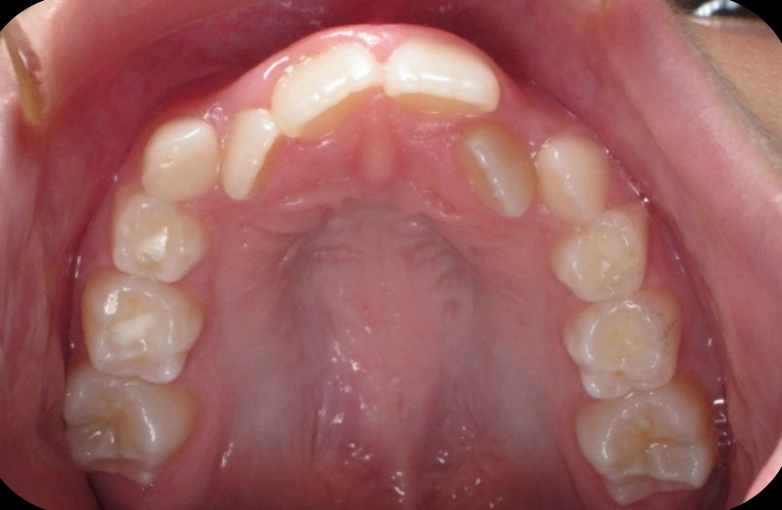

Patient treated with EXPANSION and braces

Before

After